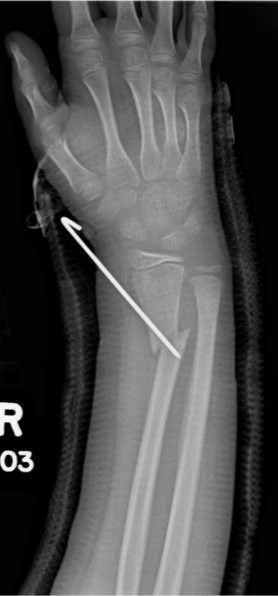

Загальна рентгенографія